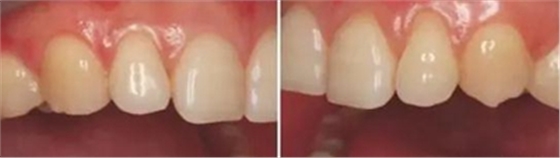

上下前牙正面影像

構(gòu)圖包含4-6顆前牙,中切牙為對(duì)焦中心

采用黑背景

拍攝比例:1:1.8,光圈f38,快門速度1/125,閃光強(qiáng)度M/4